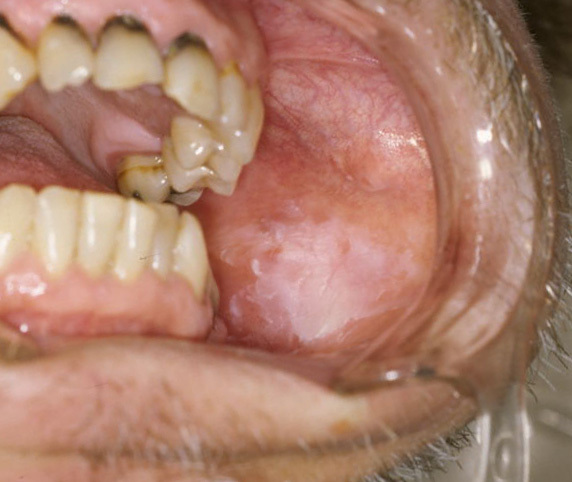

Oral Leukoplakia

Oral leukoplakia can appear as red, white, or gray patches in the oral cavity and cannot be scraped off (see Figure 3). The patches can be thick, flat, or even slightly raised, and also might have an irregular shape. These patches also can be seen as smooth, rough, fuzzy, or ridged in nature.6,7

![]() |

Photo taken of patient, who will remain anonymous, treated at the University of Tennessee Health Science Center College of Dentistry in Memphis, TN. The lesion is an example of leukoplakia. Biopsy was going to be done later to establish a specific diagnosis. |

Located on the gums, the inside of the cheeks, the bottom of the mouth, or tongue, the patches usually are painless but may be sensitive to touch, heat, or other irritation.6,7 Sometimes these patches can be sensitive or even painful when they come into contact with acidic or spicy food.

Leukoplakia can be a sign of oral cancer or a precancerous lesion. Treatment involves removing the patches with a laser or scalpel. The area should be numbed with a local anesthetic or general anesthesia. The mouth should heal quickly, and follow-up visits should be scheduled to monitor the healing process.6,7

Treatment for leukoplakia is most successful after a patch is discovered and receives early treatment when it is small. The patient’s mouth should be checked regularly for changes to the cheeks, gums, and tongue.6,7

Stopping the source of irritation (such as tobacco or alcohol use) often clears the condition. If lifestyle changes do not work or early signs of cancer are observed, the patches may be removed using a small surgical knife, laser tool, or cryotherapy to destroy the cancer cells. A referral to an ENT specialist is indicated if the primary care physician is not familiar with the procedure.2,8